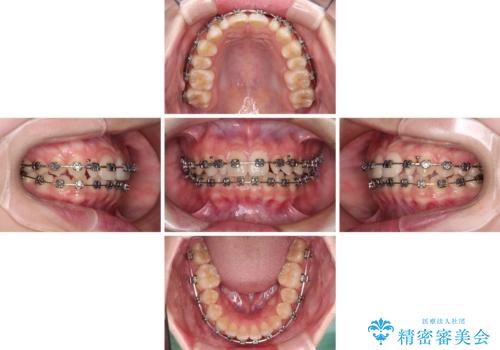

- 矯正装置

- メタルブラケット

- 治療期間

- 1年1ヶ月

- 治療回数

- 10-30回